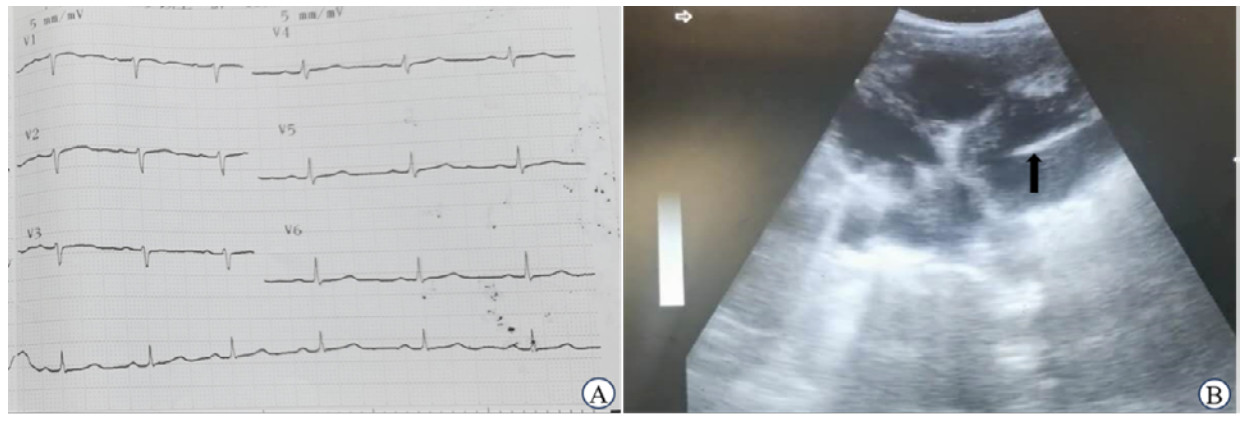

1.2 辅助检查患者实验室检查:白细胞计数7.4×109/L,空腹血糖5.9 mmol/L、血红蛋白95 g/L、血小板计数60×109/L、天门冬氨酸氨基转移酶73 U/L、丙氨酸氨基转移酶110 U/L、人体免疫缺陷病毒抗体阳性、梅毒快速血浆反应素试验阳性、乙肝表面抗原阳性,血吸虫抗体及疟疾抗原检测阴性,医院无法开展凝血功能检查。心电图未见明显心肌缺血性改变(图 1A);肝脏超声检查提示肝实质回声增强,可见弥漫分布的高回声结节,肝左叶可见一圆形无回声区,边界清除,提示肝硬化改变及肝囊肿;使用腹部超声探头于剑突下四腔心切面探查可见左心室内条状高回声,位置和形状固定,周围未探及大的血栓或赘生物影(图 1B)。

| 注:A为患者胸导联心电图检查未见明显缺血性改变(机器肢体导联损坏,纸速:25 mm/s,灵敏度:5 mm/mV);B为使用腹部探头剑突下四腔心切面探查可见左心室内条状高回声影(黑色箭头所示),位置和形状固定 图 1 患者辅助检查资料 |